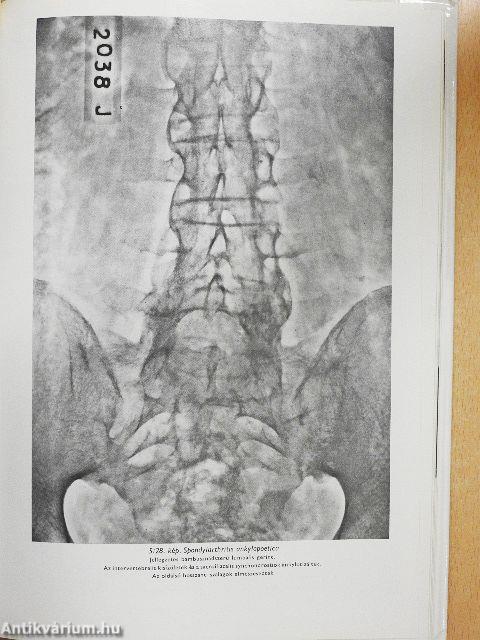

| Spondylolysis, spondylolisthesis | 309 |

| A gerinc degeneratív elváltozásai | 309 |

| Gyulladásos eredetű elváltozások | 312 |

| Spondylarthritis anklylopoetica | 313 |